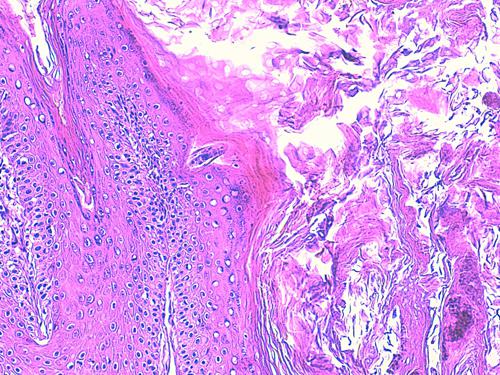

On observe une hyperplasie de l’épiderme et de la gaine épithéliale folliculaire externe en région infundibulaire, hyperplasie irrégulière associée à une alternance d’ortho et de parakératose. Les abouchements folliculaires sont dilatés, obstrués d’un matériel kératosique et pustulo-croûteux, les pustules étant riches en éosinophiles (Photo 1,2,3,4,5,6). On peut observer, au sein de l’épiderme et des abouchements folliculaires, des lésions pustuleuses dessinant de petits trajets entourés de structures épithéliales fissurées avec rupture des desmosomes intercellulaires avec un aspect focalement nécrolytique (Photo 4,7,8,9,10,11,12).

Photo 1 (Hémalun Eosine X 40) peau velue: L’épiderme et les infundibula folliculaires

sont hyperplasiques et hyperkératosiques. Les infundibula folliculaires sont le siège de pustules luminales et

pariétales, avec des fissurations linéaires parallèles au grand axe des follicules.

Le derme montre un inflammation péri-vasculaire et folliculo-centrée à diffuse.

Légendes de la Photo 1 :

- Double flèche bleue pointillée : grand axe des infundibula folliculaires à gaine épithéliale hyperplasique

- Double flèche verte : derme

- Ovales jaunes : pustules dans la paroi des follicules pileux

- Flèches jaunes : fissures linéaires dans la paroi des follicules pileux qui sont parallèles au grand axe des infundibula folliculaires

- Étoiles vertes évidées : lumière d’un follicule pileux hyperkératosique occupée par de la kératine et couche cornée hyperkératosique